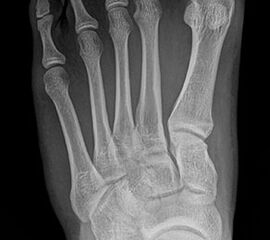

Bei einem juvenilen Hallux valgus handelt es sich um eine schon im Kindes – oder Adoleszentenalter 1 bestehende Valgusdeviation der großen Zehe bei Spreizfuß mit vergrößertem Intermetatarsalwinkel I / II aufgrund einer Adductionsstelllung des Metatarsale I – Metatarsaus primus varus.

Im Gegensatz zum Hallux valgus des Erwachsenen ist die Valgusabweichung der großen Zehe meist geringer ausgeprägt als bei Erwachsenen, der Intermetatarsalwinkel oft stark vergrößert. Die Angaben ab wann der Intermetatarsalwinkel als vergrößert gilt schwanken zwischen > 9° 2 und >14°3. Das Ausmaß der Beschwerden korrelieren nicht mit dem Auftreten und dem Schweregrad der Deformität (Zollinger 1990, Zollinger 1993). Begünstigend wirkt eine Schrägstellung des ersten Tarsometatasalgelenkes (Hefti 1998) und eine Hypermobilität dieses Gelenkes 2 in Kombination mit einer Bindegewebsschwäche. Häufig liegt eine positive Familienanamnese vor. In einer Untersuchung von Coughlin fand sich eine Vererbung über die mütterliche Linie in 72%, ein milder bis stark ausgeprägter Knick-Senkfuß in 17% (das entspricht der Quote von Knick-Senkfüßen in der Normalbevöl­kerung) aber in 22% ein Pes adductus, das ist wesentlich mehr als in der Normalbevölkerung zu erwarten wäre 4. Auch für Hefti (1998) gilt der Pes adductus als Komponente des Sichelfußes als begünstigend. Zur Inzidenz des Hallux valgus juvenilis finden sich je nach Autor verschiedene Angaben. Nach Auswertung von Schuluntersuchungen liegt die Häufigkeit zwischen 1,6 % bis 17% 56. Häufig tritt die Fehlstellung doppelseitig auf. Der Anteil der betroffenen Mädchen liegt 4-5x höher als bei Jungen (Lamprecht 2015).

Röntgen

Standard ist die belastete Röntgenaufnahme des Fußes dorso-plantar und seitlich. Günstig ist eine Röhrenkippung von 10°-20°, um die Gelenke der Lisfranc-Linie einsehen zu können.

• Hallux valgus Winkel

• Hallux valgus interphalangeus Winkel

• Intermetatarsalwinkel I zu II

• Distaler Metatarsale Gelenkwinkel (PASA)

• Form des Mittelfußknochenkopfes

• Winkel Metatarsale I Basis zum Os cuneiforme mediale

• Metatarsalindex

• Elevation/ Plantarisierung I. Strahl

• Pes metatarsus adductus

• Wachstumsfugen